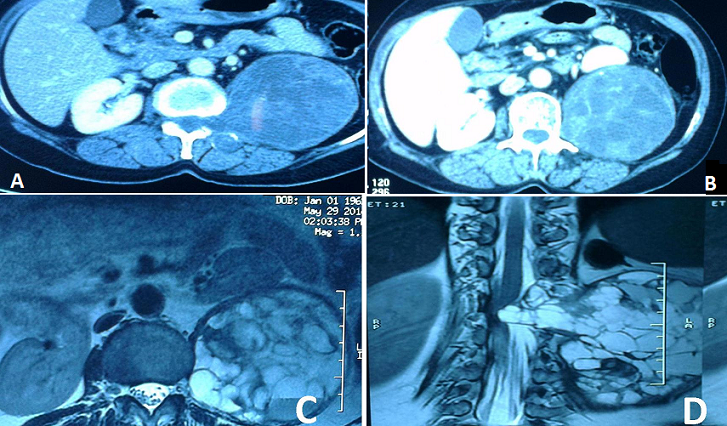

Les masses retro-péritonéales kystiques et multi-cloisonnées sont rares. Plusieurs diagnostics peuvent être évoqués devant une masse retro-péritonéale kystique et multi-cloisonnée parmi lesquels: un kyste hydatique du psoas ou une tumeur nerveuse. Nous rapportons l'observation d'une patiente âgée de 50 ans sans antécédent pathologique notable qui présente depuis 6 mois des douleurs isolées du flanc gauche. L'examen clinique trouve une patiente en bon état général avec une légère sensibilité à la palpation du flanc gauche. L'examen neurologique est normal. Le bilan biologique est normal. L'échographie abdominale est revenue en faveur d'un abcès froid ou d'un kyste hydatique du psoas gauche. Le scanner abdominal montre une masse rétropéritonéale gauche avec une composante endo canalaire et exo canalaire. Elle est de forme ovalaire majoritairement kystique, contenant de multiples cloisons épaisses et mesure 90 x 117 mm. S'agit-il d'une tumeur neurogène ou d'un kyste hydatique (A et B). Le complément IRM lombaire a mis en évidence cette volumineuse masse, bien limitée, ovalaire, multi-loculée, se rehaussant de manière hétérogène, délimitant des zones liquéfiées qui mesure 86 x 92 x 120 mm. Elle s'étend en dedans en endo canalaire, élargissant le foramen gauche de L1 et venant comprimer le cône médullaire et dissocier les racines nerveuses (C et D). La prise de contraste n'est pas en faveur d'un kyste hydatique. La patiente est adressée en neurochirurgie pour une prise en charge.